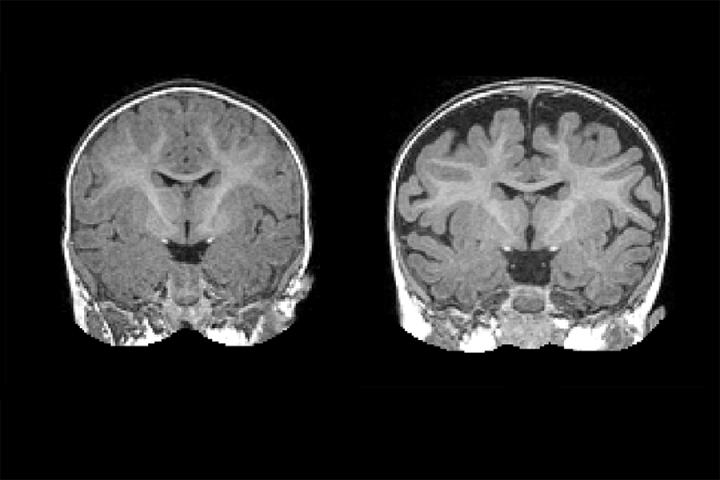

CHAPEL HILL, NC - A national research network led by UNC School of Medicine's Joseph Piven, MD, found that many toddlers diagnosed with autism at two years of age had a substantially greater amount of extra-axial cerebrospinal fluid (CSF) at six and 12 months of age, before diagnosis is possible. They also found that the more CSF at six months - as measured through MRIs - the more severe the autism symptoms were at two years of age.

The six-month olds who went on to develop autism had 18 percent more CSF than six-month olds who did not develop autism. The amount of CSF remained elevated at 12 and 24 months. Infants who developed the most severe autism symptoms had an even greater amount of CSF - 24 percent greater at six months.

"Normally, autism is diagnosed when the child is two or three years old and beginning to show behavioral symptoms; there are currently no early biological markers," said David G. Amaral, director of research at the UC Davis MIND Institute. "That there's an alteration in the distribution of cerebrospinal fluid that we can see on MRIs as early as six months, is a major finding."

The researchers found that increased CSF predicted with nearly 70 percent accuracy which babies would later be diagnosed with autism. It is not a perfect predictor of autism, but the CSF differences are observable on a standard MRI. "In the future, this sort of CSF imaging could be another tool to help pediatricians detect risks for autism as early as possible," Shen said.